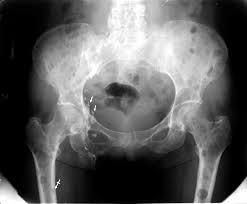

} myeloma cells produce paraproteins which are found in blood and urine (protein bence jones). The pelvis contains numerous lytic lesions without reactive sclerosis which have multiple myeloma. Healthy plasma cells help you fight infections by making antibodies that recognize and attack germs. Spotlight revised international staging system for multiple myeloma: Multiple myeloma is a cancer of plasma cells, which are white blood cells found mainly in the bone marrow. If you still can't find it, please let us know so we can add it!. Other tests include blood monoclonal immunoglobulin and radiology tests to determine the extent of bone lesions. Multiple myeloma is the second most common type of blood cancer after leukemia. 1,2,3 it accounts for approximately 1% of all malignant. Treatment response, detection of relapse. International myeloma working group molecular classification of multiple myeloma: It accounts for approximately 10% of all. Extraosseous myeloma refers to any manifestation of multiple myeloma where there is plasma cell proliferation outside the atypical manifestations of multiple myeloma: